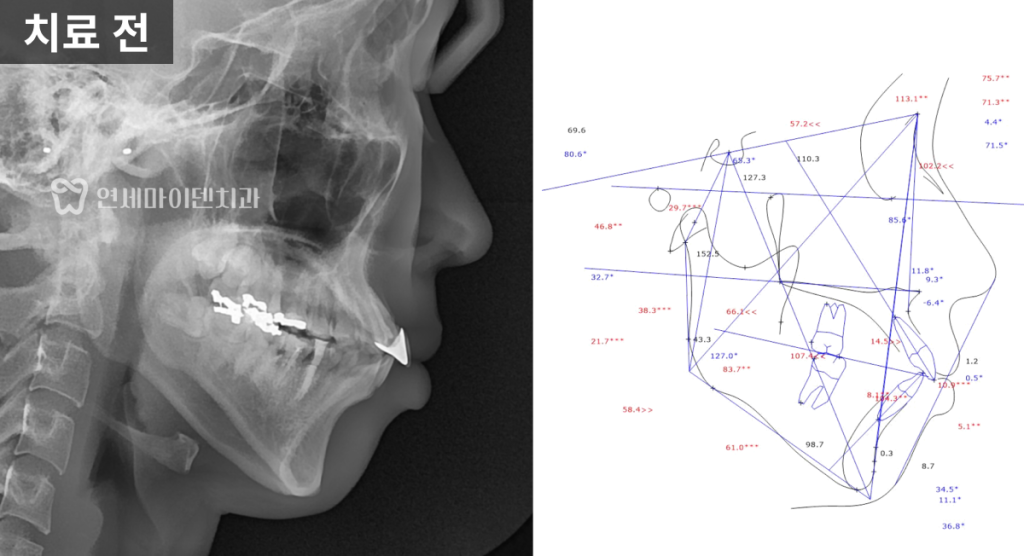

돌출입 2급 부정교합 진단

이번 케이스는 20대 돌출입 환자의

치아 교정 치료 사례입니다.

초기 검사 결과,

앞니가 전반적으로 앞으로 뻐드러져 있었고

일부 치아는 신경치료가 불완전하거나

염증이 동반된 상태였습니다.

또한 골격적으로는

위턱이 상대적으로 발달하고

아래턱이 뒤로 들어간

2급 부정교합 양상을 보이고 있었습니다.